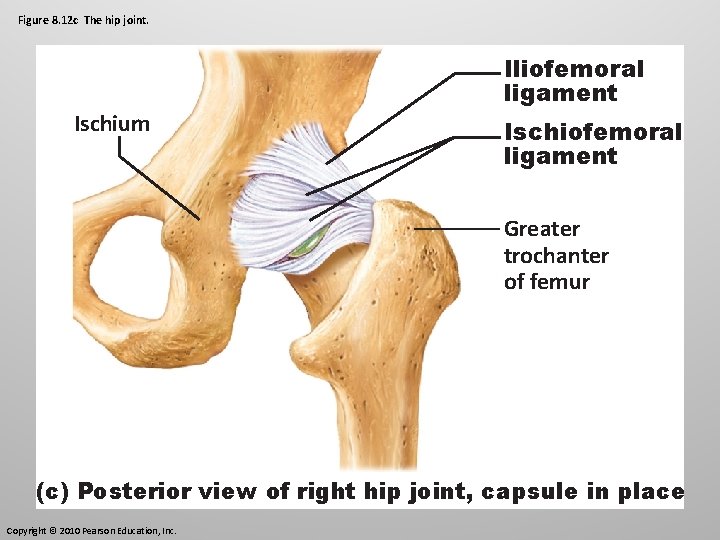

Hip (Coxal Joint) This is a ball and socket joint whose movement is limited by strong ligaments. It is formed from the spherical head of the femur and the deeply cupped acetabulum in the pelvis.

Figure 8. 12 c The hip joint. Ischium Iliofemoral ligament Ischiofemoral ligament Greater trochanter of femur (c) Posterior view of right hip joint, capsule in place Copyright © 2010 Pearson Education, Inc.

Hip (Coxal Joint) The ligamentum teres attaches the femur to the acetabulum.